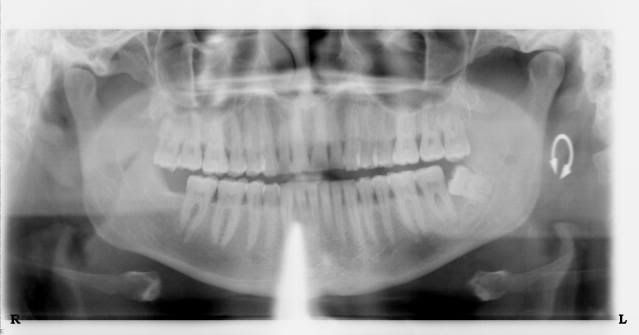

I went to the dentist today to have an impacted wisdom tooth pulled. The novicane is just starting to wear off now! ouch!!!.. When I went there last week to get all the x-rays done, there was one in particular that I just had to have for myself. Doesn't hurt to ask right?. He agreed to send it to my email... Here it is

Those things are cool. I got one of my sons skull a few years back. That was a bad tooth wasn't it.

DAM!! When you said "impacted", you meant it